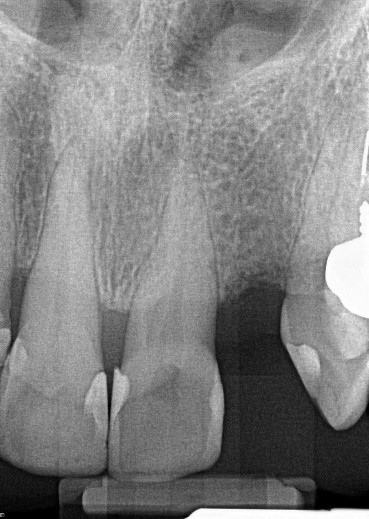

22. (Select ONE OR MORE correct answers.)

Which of the following may complicate the root canal treatment on tooth 2.2??

23. (Select ONE OR MORE correct answers.)

Which of the following may complicate the root canal treatment on tooth 2.1?